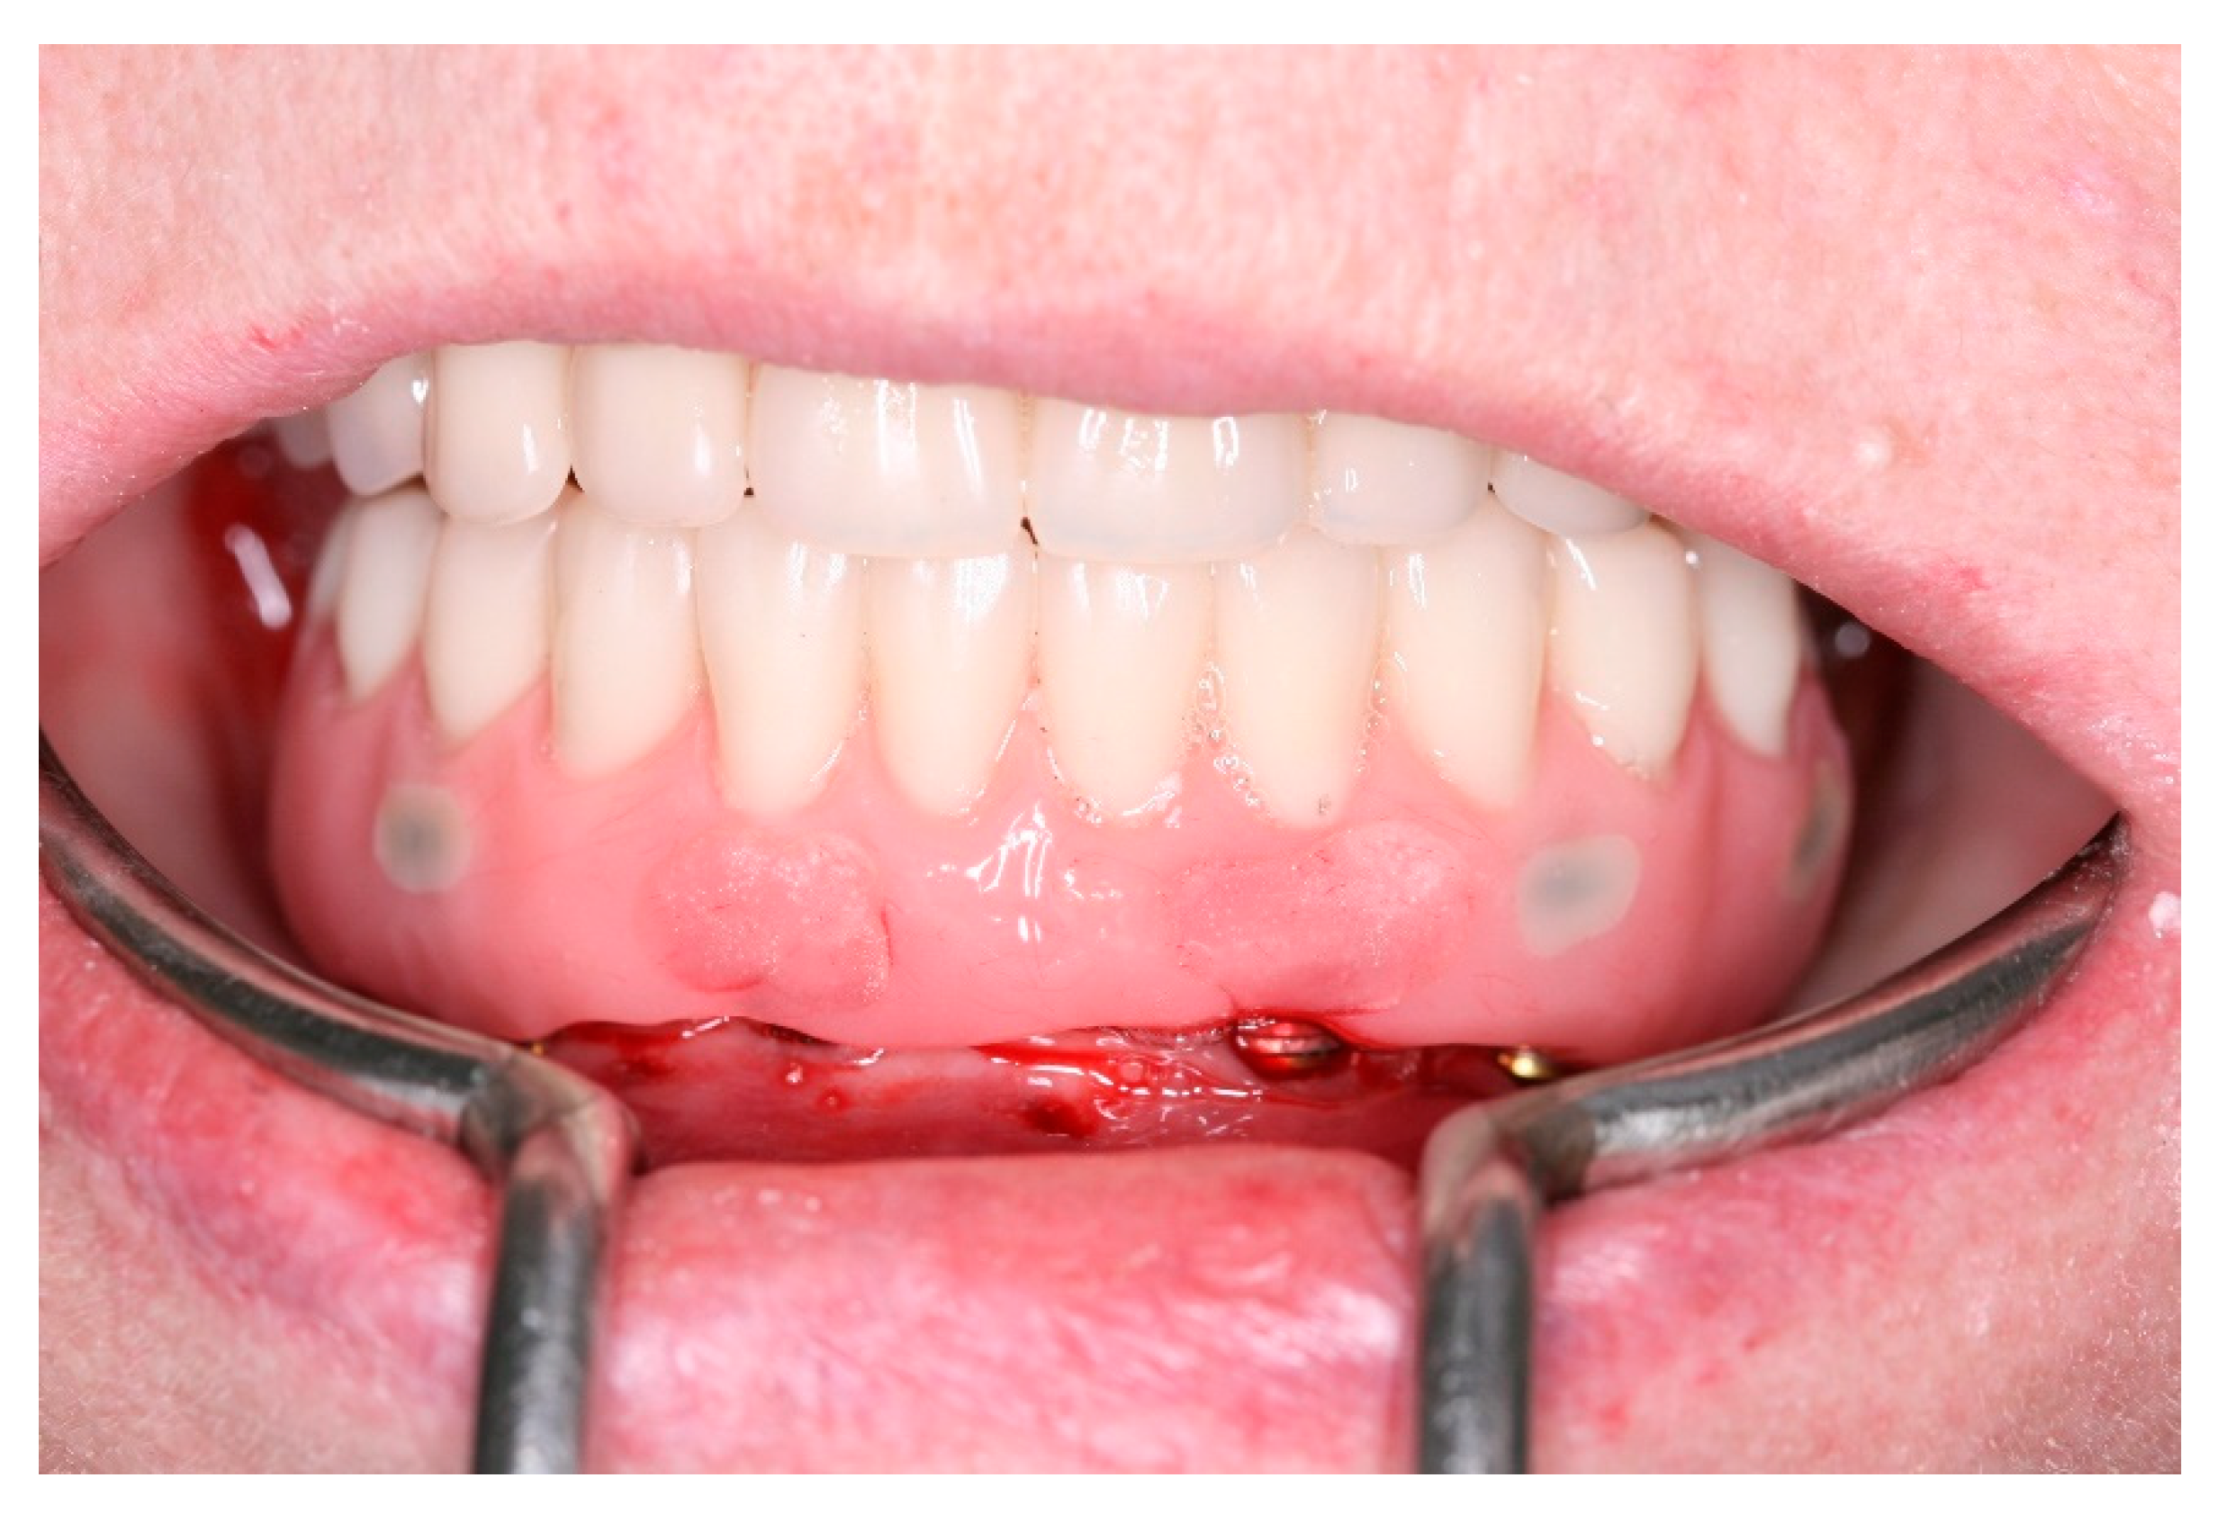

Figure 21. Buccal view of the new fixed screw-retained full-arch rehabilitation in occlusion.

After a healing period of 3 months the patient returned to change que temporary fixed prothesis for a new one, more delicate and with a reinforced metallic bar for a better ferulization of the implants and better dissipation of the stress during function. After removal of the temporary prosthesis we could see the peri-implant mucosa was healthy (Figure 19), without bleeding on probe nor peri-implant sulcus with more than 3mm depth, even around the implants were there were lack of a satisfactory keratinized tissue band, showing us that the patient was being able to maintain the cleansing of the region below the prosthesis. A new fixed rehabilitation over the implants was produced (Figure 20, Figure 21 and Figure 22). 2 years after the surgery we could see on a control panoramic radiograph no signs of bone remodeling above the expected around the implants (Figure 23).

Pre-operatory medication consisted only on 2g of Amoxicillin one hour before the procedure, as suggested by her cardiologist. On surgery day, after anesthesia with Articaine 4% 1: 100,000 (DFL, Rio de Janeiro, Brazil), the computed surgical guide was placed in position, assured by the oclusal position on both sides and the stability over the patient’s mucosa, and in this position, fixed with the fixation pins after using their drills, assuring the guide immobilization (Figure 7). After that, we followed the guided bone instrumentation protocol recommended by the Plenum implant system (Plenum® Bioengenharia- Jundiaí, Brazil) to place 4 dental implants of 4.0x10mm with morse-tapper connection, produced by addtive manufacturing technology using titanium powder grade 23 (Figure 8), without raising a flap (Figure 9 and Figure 10). Because of this detail, very little bleeding was noted during the surgery. All implants were inserted with insertion torque ranging from 45 to 60 N/cm, assuring us the possibility for immediate load. The guide was removed (Figure 11) and four mini-conic abutments (Plenum® Bioengenharia- Jundiaí, Brazil), with 2mm high were installed on the implants. No suture was necessary and minimum trauma was noted on the soft tissue (Figure 12). Over these abutments, titanium cylinders were installed (Figure 13) and the lower denture was prepared to capture the implants position, translating the removable prosthesis into a fixed one (Figure 14 and Figure 15). Pattern Resin was used to unite the denture to the cylinders, and over the red resin, pink acrylic resin was used to improve the aesthetic appearance of the prosthesis. The denture was worn out in order not to touch the patient’s mucosa, and to diminish the cantilever we removed the molars from both sides of the denture (Figure 16) and installed the temporary fixed screw retained full-arch rehabilitation (Figure 17 and Figure 18). With this, the patient left the surgical appointment with an immediate load implant rehabilitation. Post operatory medication consisted on 600mg of Ibuprofen, twice a day during 3 days, if necessary. She was instructed to put ice bags on the surgical area during 48 hours, about 15 minutes every hour. On the day before surgery the patient suspended the medication because she had no pain. The patient was also instructed not to sleep with the opposing complete denture for 7 days and feed only with soft foods.